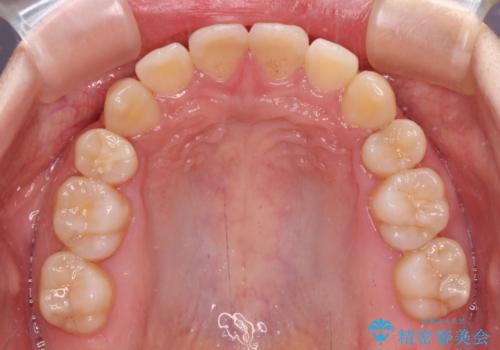

- 上下前歯が前方に飛び出しているとのことで来院された患者様です。

上下左右第一小臼歯4本を抜歯して、積極的に口元を引っ込めるよう、ワイヤー装置にて矯正治療を行うこととしました。

口元の突出感は著しく改善され、横顔の印象が大きく変化しました。